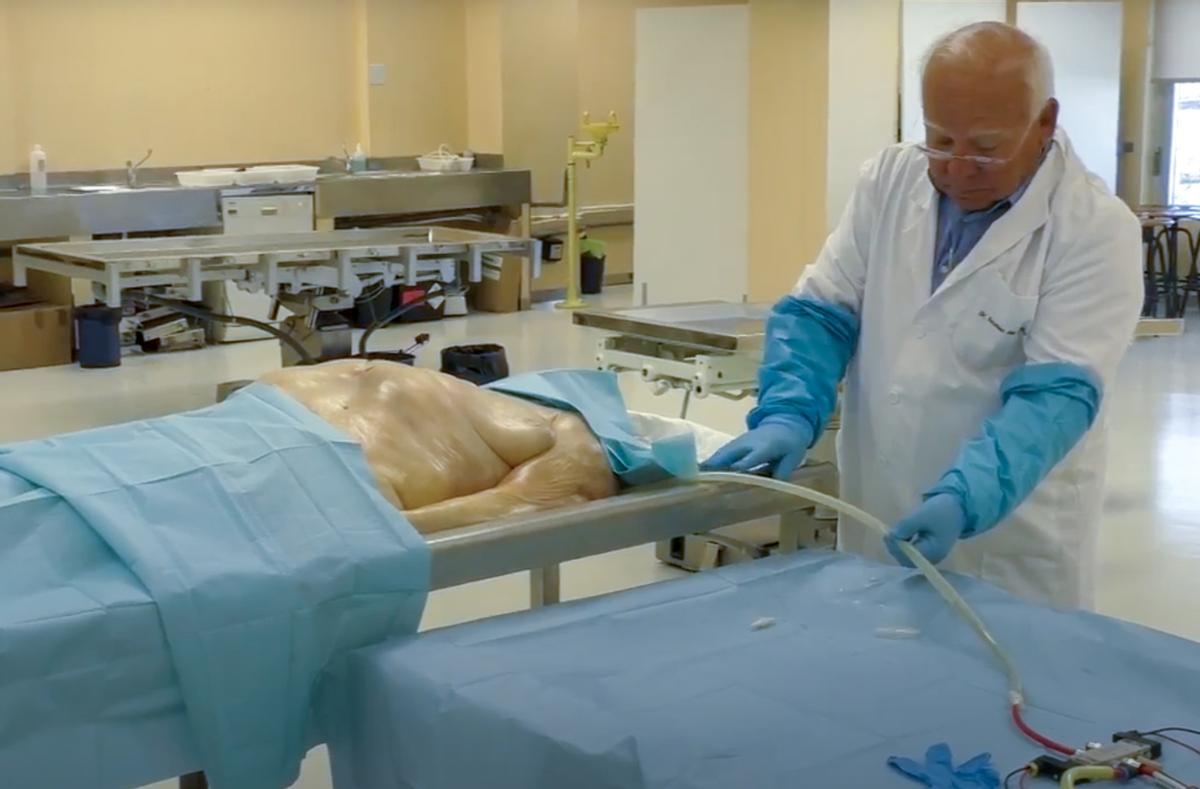

La Inteligencia Artificial también crea cyborgs, "hombres máquinas" para ayudar a los cirujanos en sus prácticas de aprendizaje con cadáveres donados a la ciencia en los que, mediante microchips que se introducen bajo la piel e impulsos eléctricos, se recrea el sistema respiratorio.

También el circulatorio gracias a unas bombas controladas por IA que simulan las diferentes tipologías de ritmos cardiacos e impulsan los que se denomina pseudosangre, que circula por el cuerpo cuando los cirujanos cortan con el bisturí.

Pseudosangre

Esa sangre artificial (colorante líquido) sale si se rompe un vaso y el cuerpo "recupera el pulso" en un simulador clínico cadavérico que está teniendo una gran acogida en la formación de cirujanos de toda España pues el modelo mantiene la flexibilidad de un ser vivo.

Cadáveres cyborg

La Facultad de Medicina de la Universidad Miguel Hernández recibe todos los años un centenar de cadáveres que ayudan a la formación de estudiantes de Medicina, Enfermería, Podología y otras, así como para que los cirujanos entrenen destrezas gracias a unos especímenes que hacen posible simular la actividad asistencial quirúrgica de alto impacto.

Un cadáver en el centro experimental Cybor sobre el que se reproducen gracias a la tecnología el sistema nervioso, el respiratorio y el cardiaco

"Les llamamos Cyborg porque son elementos que ayudan. Les dotamos de capas, circulatoria, respiratoria, les metemos tumores para que por palpación los estudiantes puedan encontrarlos y diagnosticarlos", explica Fernando Borrás, responsable del proyecto y director del Centro Experimental Cyborg.

Ahora están empezando a simular el sistema nervioso. "Queremos dotar a nuestro cadáver, que es un ser inerte, de capacidad respiratoria, circulatoria y ahora nerviosa, imitando todos los sistemas mediante tecnología, para que el aprendizaje sea óptimo".

"Les llamamos Cyborg porque son elementos que ayudan. Les dotamos de capas, circulatoria, respiratoria, les metemos tumores para que por palpación los estudiantes puedan encontrarlos y diagnosticarlos"

"Hacen falta cuerpos para la ciencia. Hacemos un llamamiento para todos los que quieran quieran donar su cuerpo a la investigación. Hacen un gran labor porque permiten, por ejemplo, a un neurocirujano trabajar con una cabeza real, y a los médicos en general mejorar sistemas. La Facultad se hace cargo de recoger el cuerpo cuando la persona fallece.

"Hacen falta cuerpos para la ciencia. Hacemos un llamamiento para todos los que quieran quieran donar su cuerpo a la investigación. Hacen un gran labor porque permiten, por ejemplo, a un neurocirujano trabajar con una cabeza real"

Otra línea con este mismo simulador cadáver se trabaja con las fuerzas militares para que los efectivos del Mando de Operaciones Especiales que se desplazan a zonas en conflicto aprendan a realizar torniquetes, suturas o atender roturas de heridos por bala o minas. Esto es posible gracias a la Cátedra de Simulación Clínica de la fundación Asisa para que militares que van a combate real puedan atender a compañeros en lugares muy alejados de los hospitales y donde no puede aterrizar un helicóptero que los recoja.

Sistemas que se utilizan en el proyecto Cyborg de Anatomía